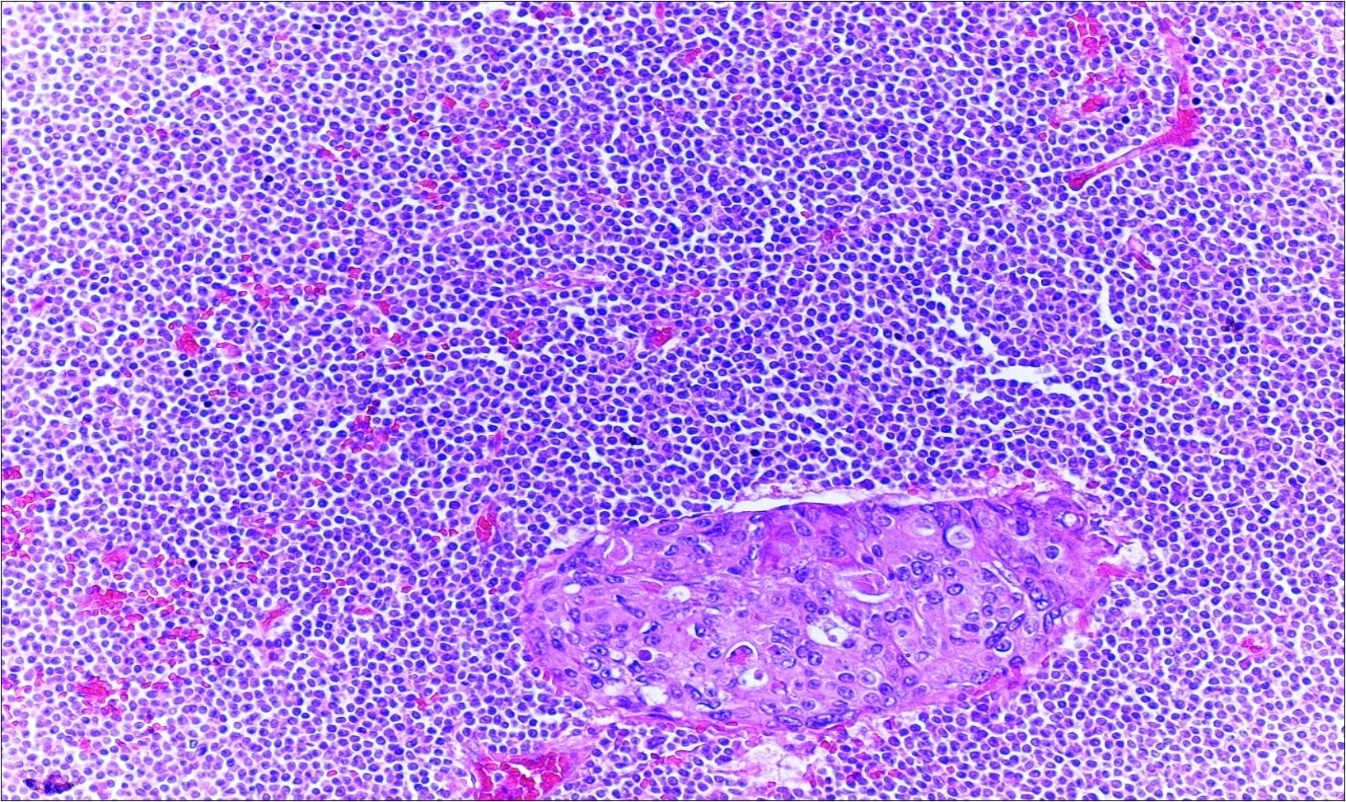

A 63-year-old woman presented to the Department of General Surgery as an outpatient with abdominal pain. Physical examination showed the signs of acute appendicitis and appendectomy was performed. During microscopic examination, a small focus of atypical monotonous lymphoid cell population was seen and the material was sampled totally. The pathological examination revealed MALT lymphoma (Figure 1), with diffuse positivity of cluster of differentiation (CD) 20 (Figure 2), CD 79a and B-cell lymphoma (Bcl- 2) (Figure 3) with just a few CD3 positive lymphoid cells. However, no evidence of adenocarcinoma was found in the appendectomy specimen. After the diagnosis of lymphoma, a complete colonoscopy was planned and this revealed a solid tumoral mass in the caecum measuring 5x4x4 cm. Computed tomography of the abdomen and pelvis revealed mesenteric lymphadenopathy associated with a mass in the caecum with multiple nodules in liver consistent with metastasis (Figure 4). Frozen sections were not obtained since the treatment method would not be affected. The patient underwent anterior resection with regional lymphadenectomy, with the pathological assessment of the resected specimen revealing a collision tumor consisting of a poorly differentiated adenocarcinoma extending through the muscularis propria with MALT lymphoma (Figure 5). Microscopic evaluation of the 11 regional lymph nodes in the mesentery of the resected colon and liver biopsy showed diffuse infiltration of MALT lymphoma with metastasis of adenocarcinoma (Figure 6). According to immunohistochemistry, atypical lymphocytes were positive for CD 20, Bcl-2, and negative for CD3, CD5, CD10, CD23, Bcl-6, terminal deoxynucleotidyl transferase, and cyclin D1. The proliferation fraction (MIB-1 immunostaining) was approximately 20%. The morphological and immunohistochemical findings were used to confirm the diagnosis of synchronous presentation of MALT lymphoma and colon adenocarcinoma within the caecum, mesenteric lymph nodes and liver metastases.

Figure 6.Adenocarcinoma with MALT lymphoma infiltration of lymph node (h&e;200)